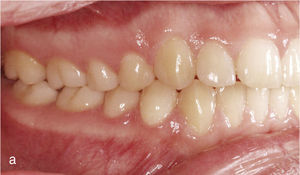

Corrección de mordida cruzadaLas mordidas cruzadas se pueden tratar con el sistema Invisalign de forma muy predecible. La corrección de la mordida cruzada posterior se puede llevar a cabo con el sistema Invisalign exclusivamente o bien combinándolo con un tratamiento previo con botones y elásticos entrecruzados. La figura 11a muestra una oclusión clase II con mordida cruzada de los dientes 16 y 46. El tratamiento con Invisalign incluyó la distalización en la arcada superior derecha con corrección de la mordida cruzada mediante expansión transversal en la región del 16. La figura 11b muestra la situación intraoral a la finalización del tratamiento con configuración de una relación clase I y de una oclusión funcional de la región molar.